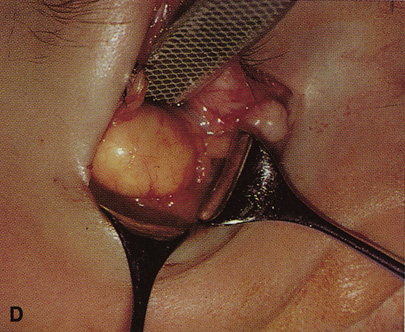

wall still can be carried out. | Fig. 9. A,B. Coronal and axial CT images of a large intraconal neoplasm. C. Because it was felt to represent a well-encapsulated cavernous hemangioma, this

lesion was a candidate for removal via an eyelid crease orbitotomy

without bone removal. The eyelid crease incision marked. D. Incision made with scalpel. E. Orbicularis muscle is tented up and incised to expose the underlying septum. F. Dissection of a skin-muscle flap deep to orbicularis exposes the orbital

septum and superior orbital bony rim. G. Cutting cautery is used to incise periosteum along the superior and lateral

rims; finger palpation of the bone helps to direct this incision. H. Periorbita is elevated along the mesial surface of the lateral orbital

rim in order to expose the deep orbital tissues. I. The cavernous hemangioma is visualized in the wound. Retraction is provided

by one or more malleable retractors. J. Cryoprobe is affixed to the hemangioma to facilitate manipulation of the

lesion. K. Large cavernous hemangioma after removal through the eyelid crease incision

which was accomplished without bone removal. L. Periorbita is reattached over the lateral rim. M. The eyelid crease incision is closed with a running suture. |